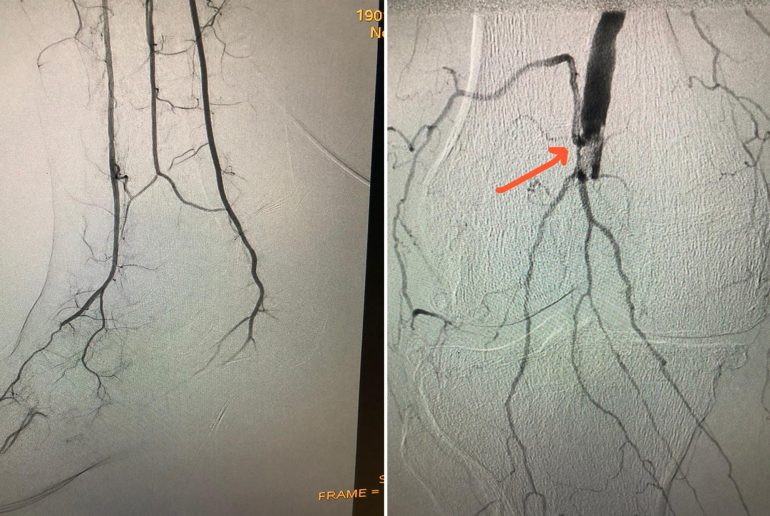

وطلب الفريق الطبي استشارة استشاري أمراض القلب التداخلية فوضع خطة علاجية مغايرة، حيث تدخل بالقسطرة عبر الجلد مع الاستعاضة عن “الصبغة الظليلة”، بتقنية جديدة هي التصوير عبر استخدام غاز ثاني أكسيد الكربون، وتم في العملية التي استغرقت نحو ساعة ونصف الساعة سحب الخثرات عن طريق القسطرة، وزراعة دعامتين مكان الانسداد الشرياني واستعادة التروية الدموية لكافة الأجزاء المتأثرة من القدم.

وقال د. الحجيلي إن العملية تعد من العمليات النادرة، وقد نجحت بامتياز بتوفيق من الله، وأثبتت التحاليل الطبية وصور الأشعة عودة جريان الدماء في كافة أجزاء القدم المصابة وتحسن الوضع الصحي للمريض، حيث غادر المستشفى معافى بعد “48” ساعة من التنويم والمتابعة الطبية.